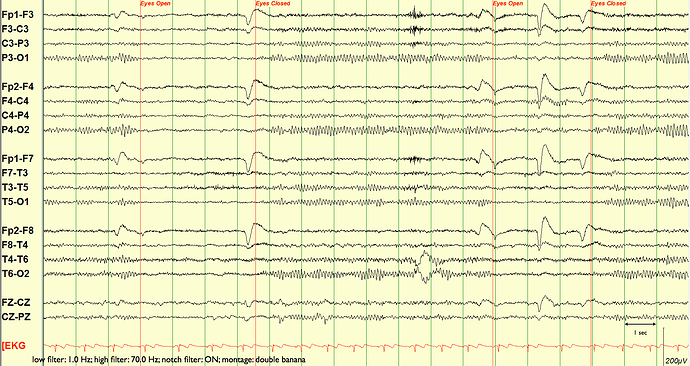

I’m simply trying to group electrodes as they would be in a usual clinical montage, rather than all the channels being equally spaced. See attached picture (does not have to be re-montaged to bipolar but even if it is in bipolar I’d like to be able to gorup)